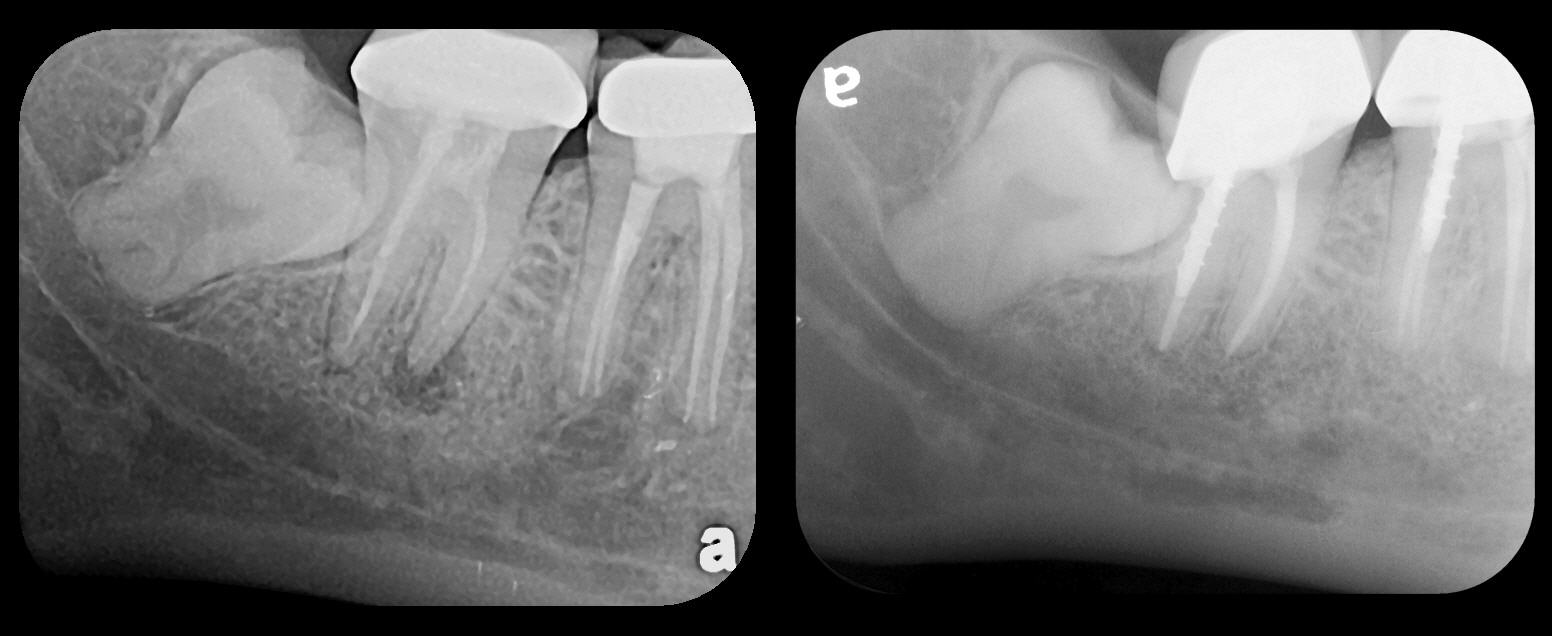

There are two specific types of DIDR sensor systems available to dentists in the marketplace: the hard-wired (HW) sensor and the photostimulable phosphor (PSP) sensor,1,2 also commonly known as phosphor "plates." A desirable feature common to both modalities is the ability to expose either bitewing (BW) or PA radiographic images. The BW radiograph (Figure 1) is usually considered more appropriate for caries detection, whereas the PA (Figure 2) is diagnostic for several different anatomic and pathologic issues.7

Fig 1. Left: Representative PSP BW radiograph with multiple restorative materials of varying radiographic densities. Tooth No. 31 demonstrates deep

caries on mesial aspect beneath the restorative. Radiolucency of carious lesion results from the low relative density of caries compared with healthy

tooth structure. Right: PSP BW radiograph optimized for view of multiple interproximal carious lesions.

Figure 1